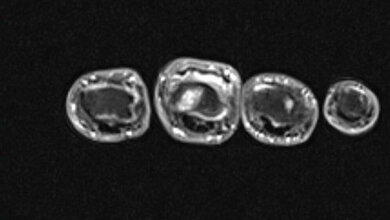

Die interdisziplinäre Studie, die vom DFG-Sonderforschungsbereich 655 und der José Carreras-Stiftung unterstützt wurde, untersuchte erstmalig die Auswirkungen alternder Blutstammzellen auf den Knochen. Die Untersuchungen wurden anhand von Mäusen mit MDS sowie Daten von etwa 980.000 Menschen durchgeführt. Ähnlich wie Menschen entwickelten die untersuchten Mäuse erst im Alter ein MDS. Dabei wiesen sie bereits vor dem Knochenmarksversagen eine deutliche Ausdünnung der Knochenstruktur auf. „Die Befunde zeigen eine Voralterung des Knochens mit hoher Fragilität“, erklärt Professor Lorenz Hofbauer, Direktor des UniversitätsCentrums für Gesundes Altern. Doch trifft dieser Zusammenhang auch bei Menschen mit MDS zu? Diese Frage wurde anhand aufwendiger Datenanalysen von Diagnoseschlüsseln und Medikamentenverordnungen von knapp einer Million bei der AOKPlus Versicherten aus ganz Sachsen beantwortet. „Patienten mit MDS besitzen ein zwei- bis dreifach erhöhtes Risiko für eine Osteoporose, es betrifft Männer und Frauen gleichermaßen“, erläutert Professor Jochen Schmitt vom Zentrum für Evidenzbasierte Gesundheitsversorgung der Hochschulmedizin Dresden.